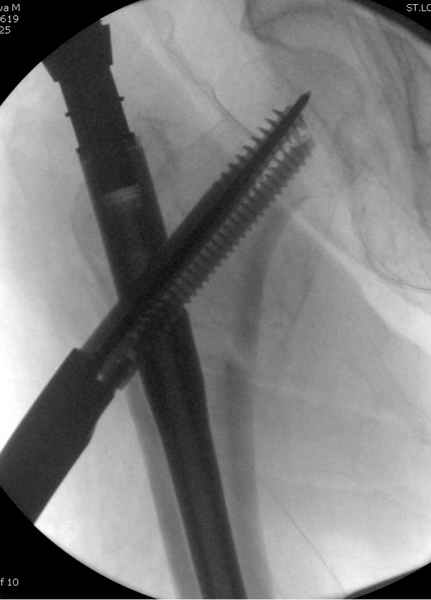

Здесь сканнированные снимки импланта и операционные снимки больной.

На этом снимке процесс компрессии нижним болтом.